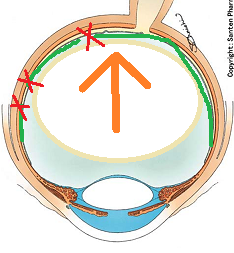

黒目(角膜)から入ってきた光は、目の奥の方のフィルム(網膜)に当たります。網膜は一つの束(視神経)になって、最終的には脳ミソにつながり、「物が見える」という事になります。

図の赤矢印の部分は視神経乳頭と言って、網膜が集まって束になる部分なのですが、実はこの部位のみ光を感じ取ることはできないのです。

写真だと水色の部分が視神経乳頭(マ盲点)になります。ちなみに、物を見る中心部の網膜は黄斑と呼ばれ、オレンジの矢印に当たります。

自覚的には、マリオット盲点(視野が欠けて見えない部分)は、視界の中央から少し外側に存在します。(正確には、中心部から外側に15度位の部位)

人間の脳は非常によく出来ていて、眼球としては光を感じない部位が存在しても、脳ミソ的には、その部位を「黒」とはしないで、その周りの色をクシャっと引き寄せて、あたかも何かが存在しているように画像を変換してしまうのです(filling inと呼ばれます)。